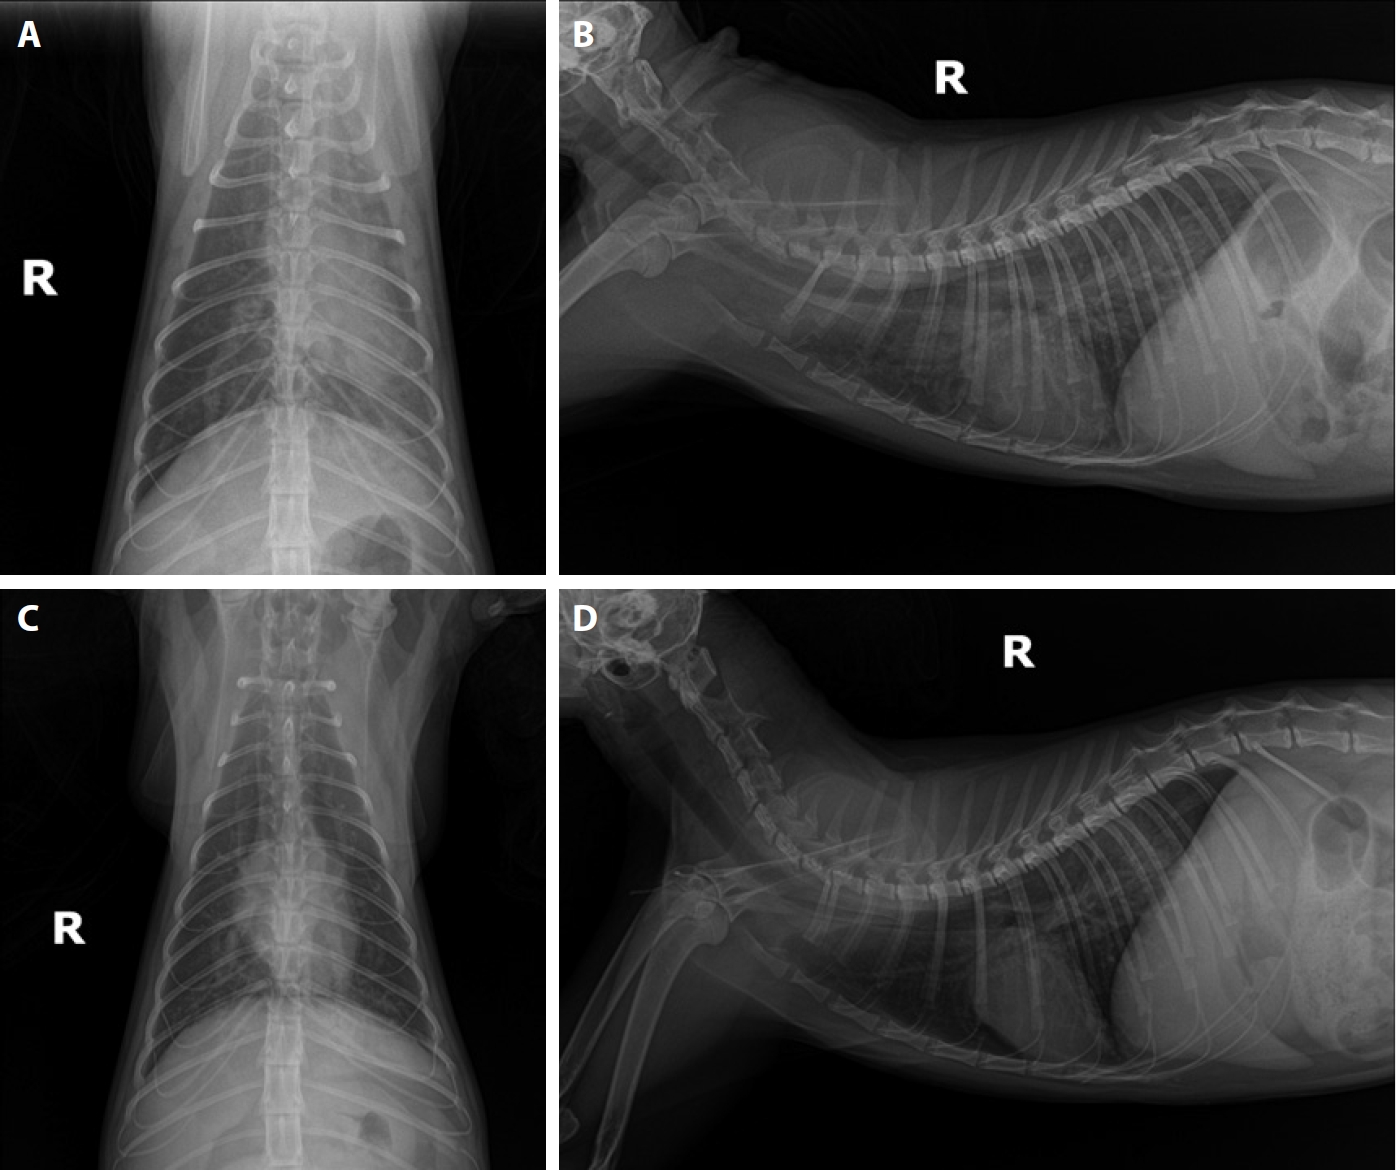

A 5-year-old rescued female stray cat presented with generalized skin ulcers, maggot infestation, and cachexia in August 2019. CBC, serum chemistry, electrolyte analysis, proBNP, FeLV and FIV tests, heartworm antigen and antibody kit tests, thoracic and abdominal radiographs, and abdominal ultrasound were performed. Test results were positive for heartworm antigen and antibody tests, anemia, dehydration, and azotemia. Thoracic radiographs revealed marked dilation and tortuosity of pulmonary arteries coursing through both caudal lung lobes. B-mode echocardiography revealed multiple hyperechoic, parallel double lines within the main pulmonary artery bifurcation and right pulmonary artery branches, consistent with adult heartworms. Standard short-axis, M-mode, and Doppler echocardiography demonstrated a normal left atrium-to-aorta ratio (1.36), preserved systolic function (fractional shortening: 56.3%), and no evidence of severe pulmonary hypertension. These findings confirmed the presence of multiple adult heartworms (

Fig. 2).

20]. With appropriate management, the cat has survived for 4 years following diagnosis and has remained asymptomatic to date. In Case 2, echocardiography played a pivotal role in confirming heartworm infection in this cat, demonstrating characteristic imaging findings. B-mode imaging revealed multiple hyperechoic, parallel double lines in the main and right pulmonary arteries, a pathognomonic sign of adult heartworms. Echocardiography showed normal chamber sizes, preserved systolic function, and no severe pulmonary hypertension, underscoring its value for detecting early or asymptomatic infections and complementing antigen testing.

Fig. 2.Echocardiographic findings in Case 2. (A, B) B-mode image showing multiple hyperechoic, parallel double lines (white arrows) within the bifurcation of the main pulmonary artery (PA) and branches of the right PA, consistent with intraluminal adult heartworms. (C) Right parasternal short-axis view at the level of the aortic root showing a left atrium (LA)-to-aorta (AO) ratio of 1.36, indicating no overt left atrial enlargement. (D) M-mode echocardiography demonstrating normal left ventricular wall motion and systolic function (fractional shortening: 56.3%).